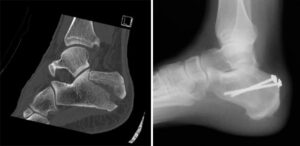

(Left) In some injuries, the talus is forced downward and acts like a wedge to fracture the calcaneus. (Right) This computerized reconstruction of a calcaneus fracture shows the amount of damage that can occur.

Surgical Procedures

- Percutaneous Screw Fixation: When bone fragments are large and can be realigned without a large incision, screws are inserted through small incisions to stabilize the fracture.

(Left) A displaced fracture of the calcaneus. (Right) The fracture has been reduced and the bones held in place with screws.